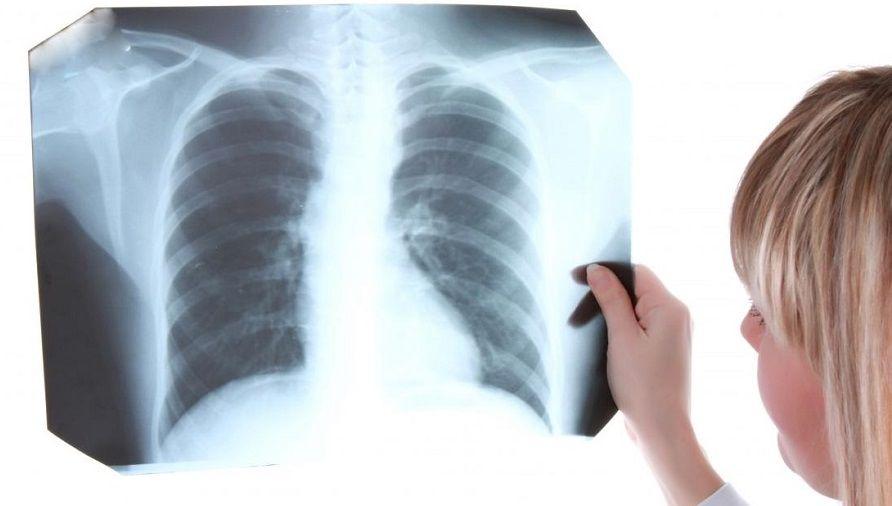

En pandemia se incrementó la mortalidad por tuberculosis por menos diagnósticos

La tuberculosis es la enfermedad infecciosa que más muertes causa en todo el mundo: unos 1,5 millones cada año, según estadísticas de la Organización Mundial de la Salud (OMS). En Argentina se incrementaron las...